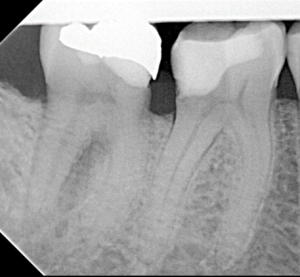

Root Canal / Retreatment

Clinical Cases